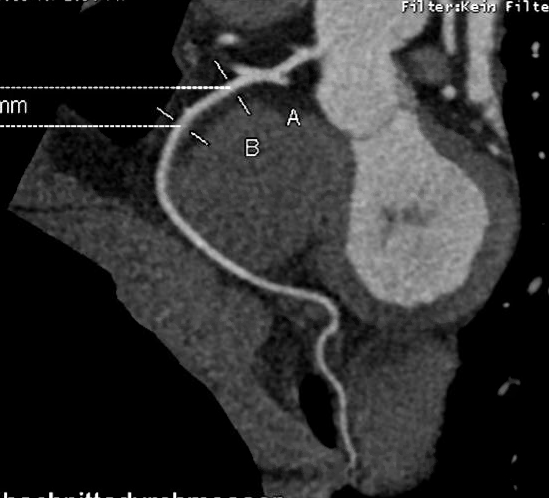

Die wCAR AUSTRIA Study ist eine multizentrische Beobachtungsstudie zur frühen Erkennung von Herz-Kreislauf-Risiken bei Frauen in Österreich. Untersucht werden 600 Frauen im Alter von 40 bis 65 Jahren. Ziel ist es, klassische und frauenspezifische Risikofaktoren systematisch zu erfassen und im Women’s Cardiovascular Risk Score (wCAR-Score) abzubilden.

Herz-Kreislauf-Erkrankungen sind die häufigste Todesursache bei Frauen in Österreich. Trotzdem gelten sie in der öffentlichen Wahrnehmung noch immer als „männliche“ Erkrankungen. Frauen zeigen jedoch oft andere Symptome, andere Risikofaktoren und andere Krankheitsverläufe.

Die wCAR AUSTRIA Study macht diese Unterschiede sichtbar und prüft, wie ein gendersensibler Risikoscore Prävention und medizinische Versorgung verbessern kann.